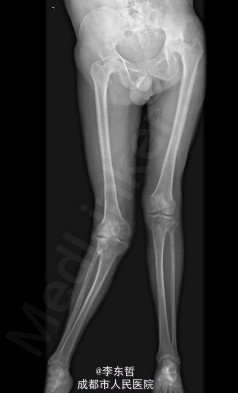

查体:生命体征平稳,心肺腹未见异常;跛行,双左下肢较右下肢短缩1cm,左、右腹股沟中点深压痛,左、右髋叩击痛,左髋屈20°,伸0°,外展10°,内收10°,右髋屈60°,伸0°,外展20°,内收20°。双髋内、外旋活动受限,诱发疼痛,左侧重。 辅助检查:x线片示双侧股骨头坏死、塌陷变形,左侧明显,左髋半脱位。

初步诊断:1、左侧股骨头坏死伴内收肌挛缩(Ficat IV期);2、右侧股骨头坏死(Ficat IV期);3、右膝骨关节炎伴外翻畸形;入院后积极完善术前检查及准备,择期行手术治疗。